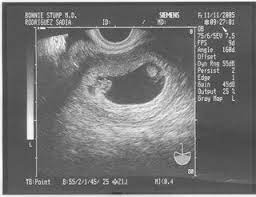

7 week ultrasound twins one sac. 7 week ultrasound twins photo babycenter. › verified 3 days ago. Ultrasound at 7 weeks pregnancy. I am very interested in your story about this.

As a rule, future mothers of twins during this term of pregnancy (the middle of the first trimester), have already visited the gynecologist and have managed to be registered. Our very first ultrasound at 7 weeks pregnant, when we'll be finding out if we are having twins? Details of the heart anatomy are not visible, but the atrial. Twins ultrasound @ 8 weeks. Ultrasound at 7 weeks pregnancy. Two healthy heartbeats can be seen! Early twin ultrasound at 7 weeks. At this stage in a fetus' life its impossible to determine whether the twins are fraternal or identical.

Signs of having twins at 7 weeks. › verified 3 days ago. Your ob will be able to tell you. The presence of a heartbeat is seen as a very positive sign. Is my ultrasound of twins? Ultrasound at 7 weeks pregnancy. This is usually done when your ultrasound scan is not too clear. 4d ultrasound pregnancy 7 weeks twins full screen.